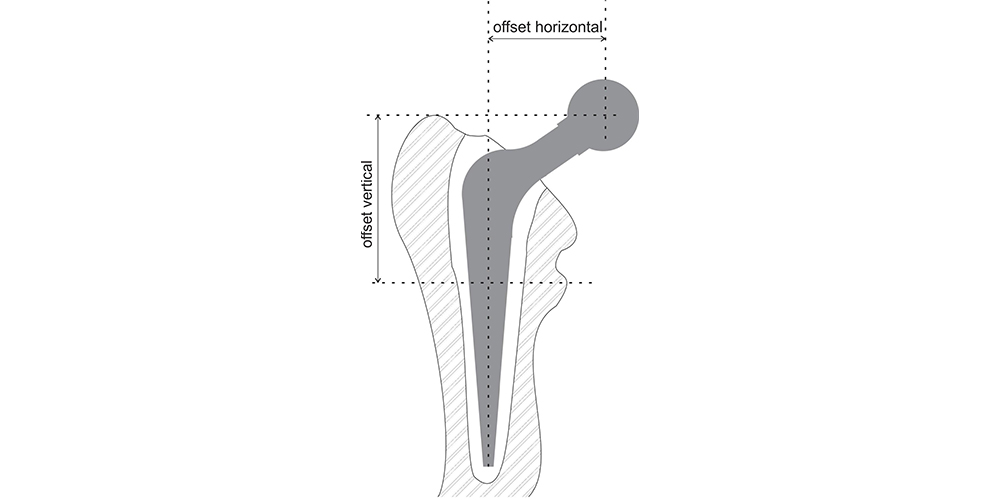

A reconstrução ideal do quadril reproduz o centro normal de rotação da cabeça femoral, sendo esta determinada pela altura vertical (offset vertical), offset horizontal (ou simplesmente offset) e a anteversão do colo femoral (offset anterior)(Fig. .5). O offset vertical e horizontal aumentam com o alongamento do colo da haste femoral. O comprimento do colo pode ser modificado através do uso de cabeças femorais modulares que se encaixam em um cone Morse no colo da haste. A haste com colo variável oferece uma oportunidade para correção da altura vertical da cabeça, que pode ser medida, por exemplo, entre o centro da cabeça e o trocânter menor. Um offset horizontal restaurado inadequadamente para menor pode resultar em aumento da força necessária da musculatura abdutora, acarretando em claudicação, impacto ósseo e luxação. O inverso causa aumento de tensões na haste e no manto de cimento, com possível fratura ou soltura da haste (2,4,7).